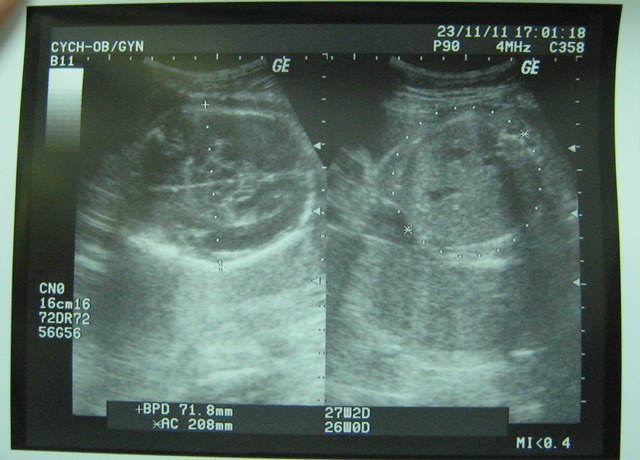

然我上拜突然肚子很痛,後不敢吃西,重少了2公斤,但瓦力是稍微成,主治他目前的重是1010公克!

最近感到胎的位置改,我以瓦力胎位正,果去就知道他的位置仍然有改。